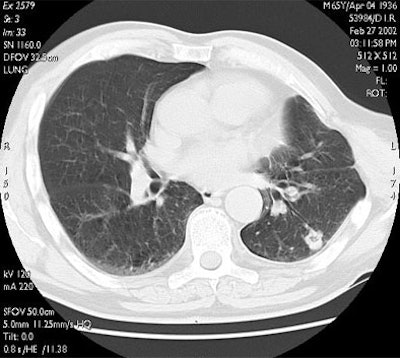

![]() |

| RF ablation of stage IA non-small cell lung cancer (NSCLC). Above: Pretreatment CT scan shows solitary small NSCLC of left lower lobe. Below: At CT obtained one month after RF ablation, a ground-glass density ablation zone replacing the lesion and 1-cm of surrounding pulmonary parenchyma is detected. Images courtesy of Dr. Riccardo Lencioni. |

"Here you can see one of the cases with a one-year follow-up. The tumor is replaced by a volume of coagulation, which is in excess with respect to the size of the native lesion, and then at three months, six months, and one year there is progressive shrinkage of the coagulation, with some cavitation detectable on CT," he said.